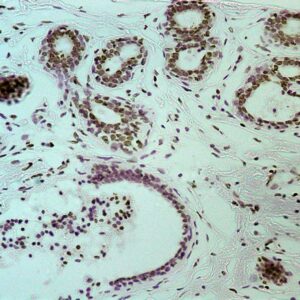

BioGenex has pioneered the development of miRNA research and diagnostics tools with leading-edge products. Currently, we offer over 240 ready-to-use (RTU) Super Sensitive™ Nucleic Acid (SSNA) miRNA ISH probes for accurate and early tumor diagnosis. These probes are sensitive enough to detect low-abundant miRNA(s) that are often required to identify biomarkers. They have a high melting temperature enabling stringent washes to remove non-specific binding. BioGenex miRNA probes are dual-end labeled with an anti-fluorophore to amplify the signal and yield clean and intense staining.